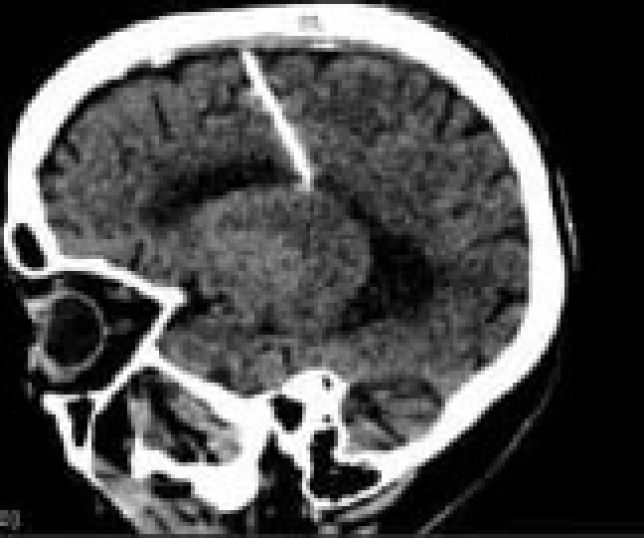

Ao realizar exames, idosa descobre agulha de 3 cm enfiada no cérebro